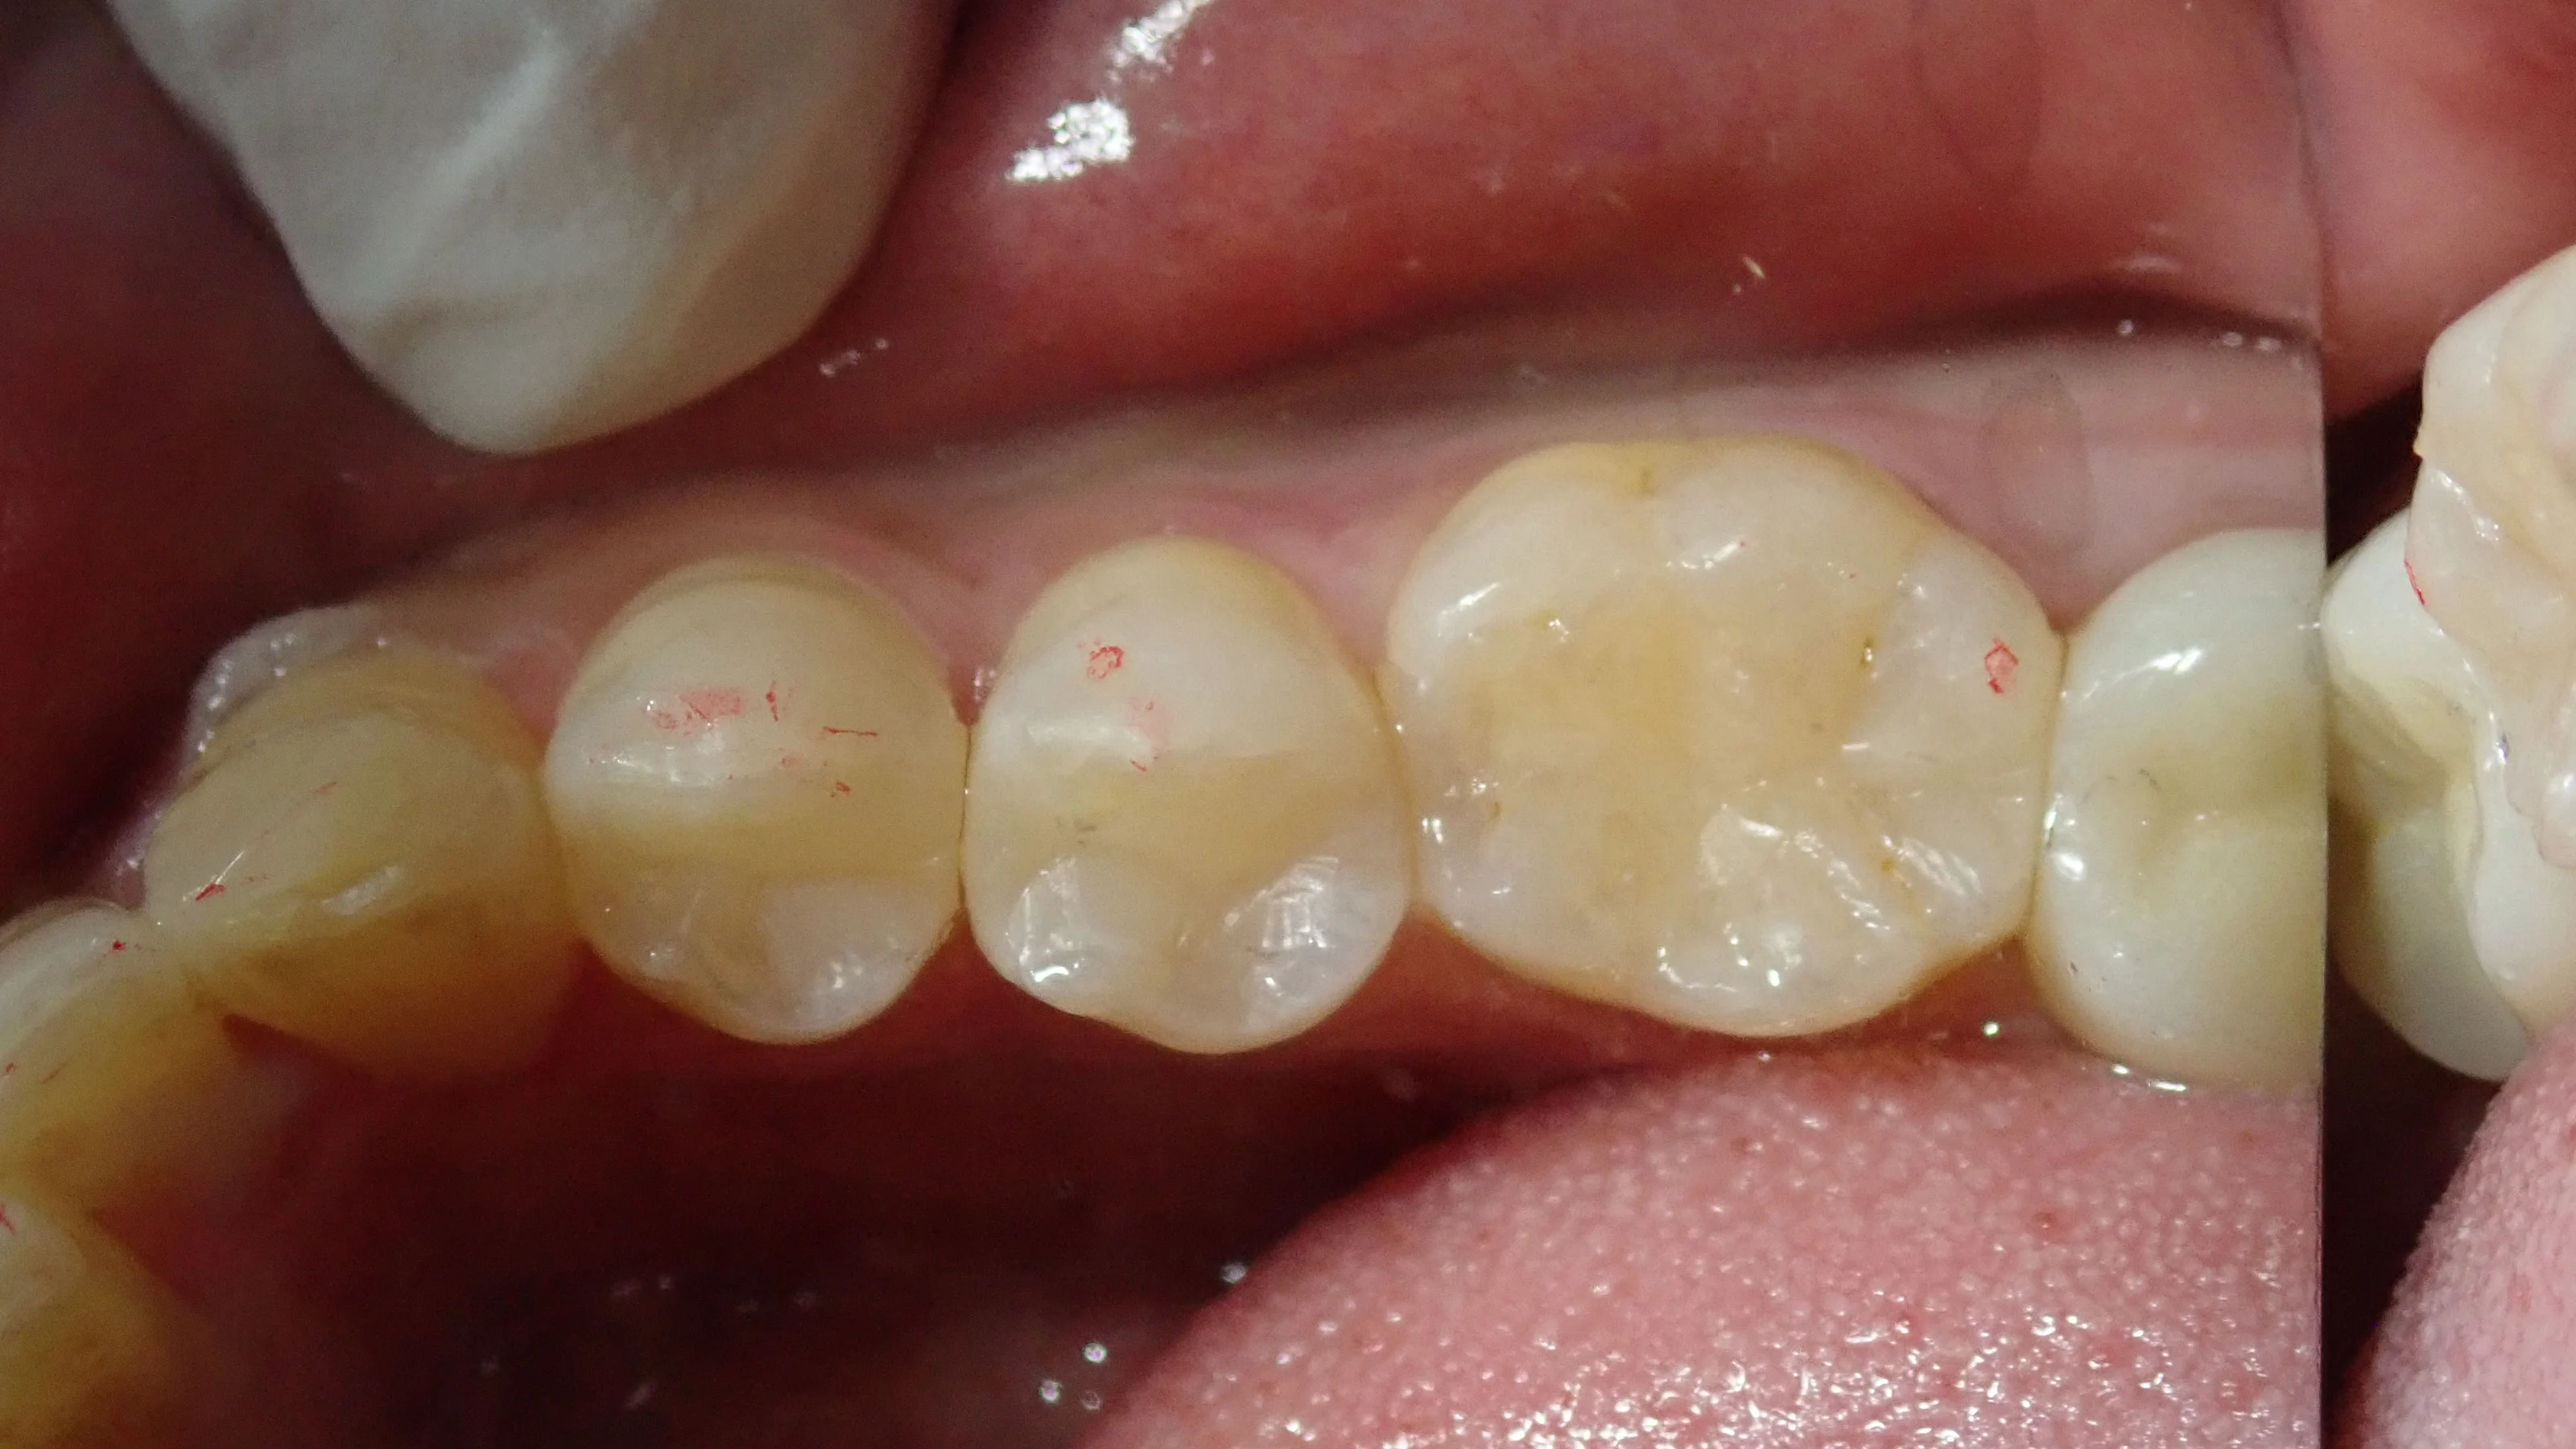

で、最終的に詰め終わったのがこちらです。

赤い部分はかみ合わせが当たる所なのですが、ここに詰め物と歯のラインなどが来なければ特に問題はありません。

(まぁこれは金属でも一緒ですが・・・・)

適合も良く、フロスなどの引っ掛かりも特になかったので、あとはTCHなどの力のトラブルがなければ十分に持たせられると思います。

ただ、これは通常保険診療では金属の詰め物・被せ物になるレベルの虫歯ですので、あまり参考にはしないでくださいね。